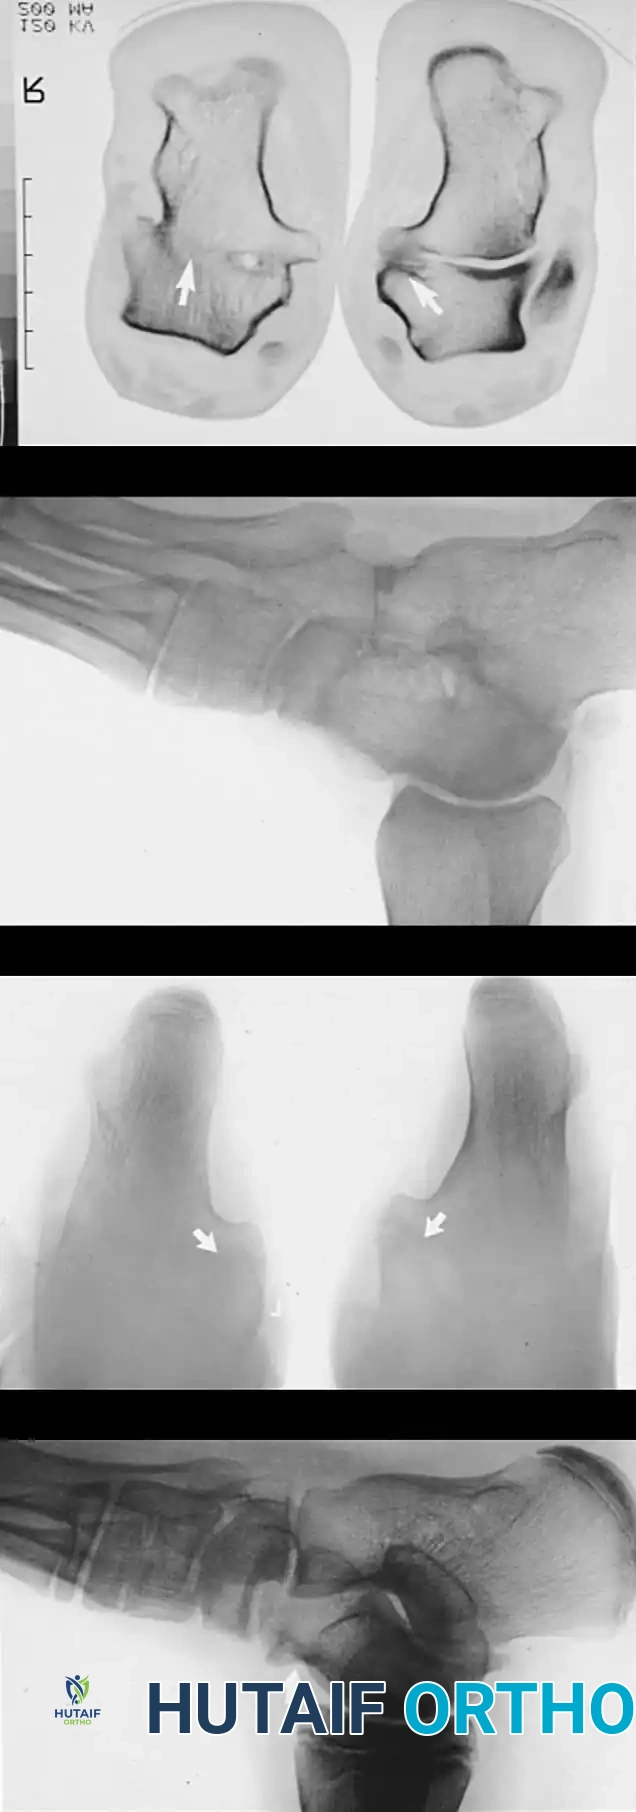

- الأشعة السينية (X-rays):

- للتشخيص المبدئي، يتم التقاط صور بوضعيات خاصة.

- لتشخيص التحام العقب والزورقي، تعتبر الصورة المائلة بزاوية 45 درجة هي الأفضل.

- لتشخيص التحام الكاحل والعقب، يتم استخدام وضعية خاصة تسمى (Harris-Beath view) لتصوير المفصل الأوسط.

- الأشعة المقطعية (CT Scan): تعتبر المعيار الذهبي لتشخيص التحام الكاحل والعقب. توفر صوراً ثلاثية الأبعاد ومقاطع عرضية دقيقة توضح حجم الالتحام، موقعه، وحالة المفاصل المجاورة، مما يساعد الجراح في التخطيط للعملية.

- الرنين المغناطيسي (MRI): قد يستخدم في بعض الحالات لتشخيص الالتحامات الليفية أو الغضروفية التي قد لا تظهر بوضوح في الأشعة السينية أو المقطعية.